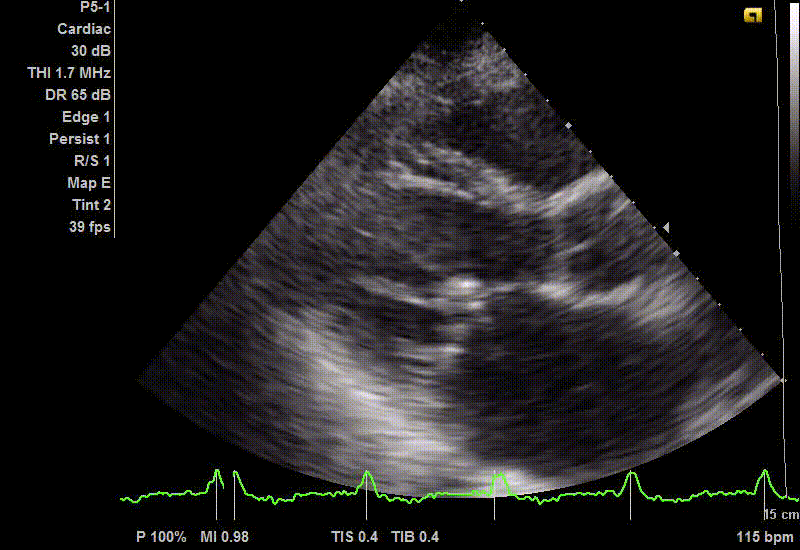

✅Эхокардиография с цветным "окрашиванием"- позволяет хорошо рассмотреть внутренние структуры сердца, работу клапанов и насосную функцию самого сердца в целом.